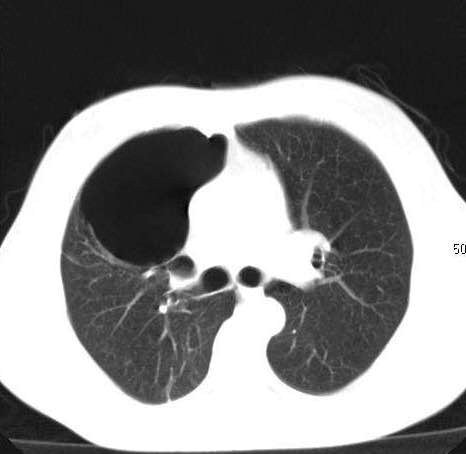

故事二、肺部磨玻璃结节别纠结

徐先生(化名)被查出肺部磨玻璃结节已有数月,且有三个——最大的约7mm,最小的5mm左右。自此,他陷入了惶惶不安,四处寻医,遍查医典,掌握了十分丰富的与肺部结节相关的医学知识。但他还是无法作出决定——开刀,或不开刀?

后经过王剑飞的一番分析与开导,徐先生终于决定手术,术后诊断——最大的是微浸润癌,其余2个是原位癌。虽然从预后看,开刀早晚差别不大,但徐先生终于安心了,又能轻松面对生活了。而对于王剑飞能想病人所想,细心考虑每一个患者的顾虑,徐先生感到十分暖心及感激。

转移前手术切除,在最大限度保留健康肺组织同时尽可能彻底切除病变肺组织,人性化考虑结节患者的处理策略——是该中心始终坚持的三大原则,他们希望每一位患者都能获得充分的诊疗,放心随访、安心开刀,能真正再次拥抱美好生活。